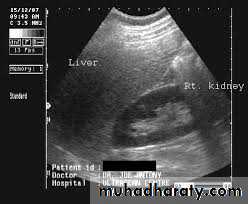

Renal ultrasound is a simple noninvasive examination .The kidney is bean shaped and has bright central echoes because of the fat surrounding the collecting system.

Normal renal ultrasound.

A longitudinal view of the right kidney was obtained by passing the sound beam through the right lobe of the liver. The kidney is seen behind this, outlined by the markers. The central bright echoes in the kidney are due to fat around the collecting system.